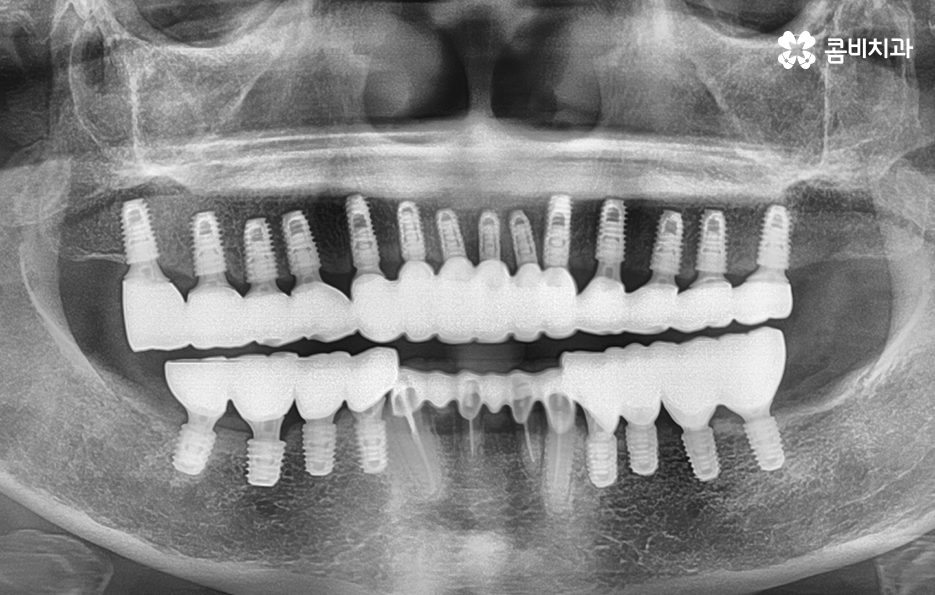

순차적으로 식립이 진행되고 있는 모습

위 사례와 같이 대부분의 치아를 잃게 되신 분들의 경우에는

임플란트가 건강하게 자리를 잡을 수 있도록

시술 과정에 있어서 심혈을 기울여야 합니다.

여러 치아를 잃게 되었을 때 또 한 가지 꼭 유념해야 하는 것은 식립 각도에 따라서 심미적으로

큰 차이가 날 수 있으며 전체적인 교합이

잘 맞물려야 하기 때문에 풍부한 경험과

실력이 필요한 진료에 해당합니다.

임플란트의 기본적인 원리는 잇몸뼈(치조골)에 식립을 하여

단단하게 고정이 된 상태에서 보철물을 씌워

자연치아와 비슷한 역할을 하게 되는 것인데

이때 가장 중요한 부분이 치조골에 얼마나 건강하고

단단하게 고정이 되느냐입니다.